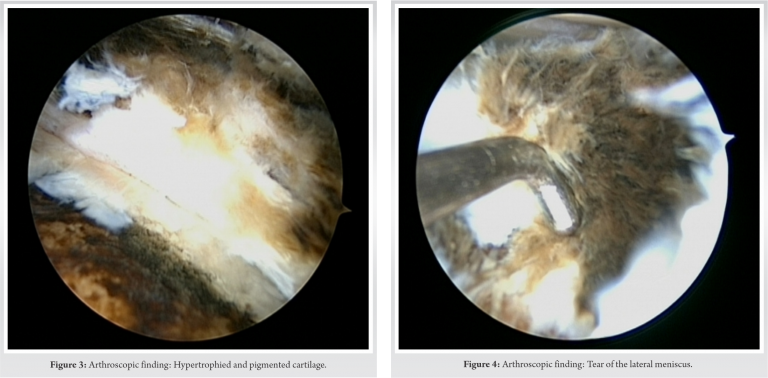

Arthroscopic findings revealed hypertrophied and pigmented synovium (Fig. 3). There were small chondral defects of size 3 mm to 5 mm, Grade 2+ more over the lateral condyle than the medial condyle. There were pigmented loose bodies with size varying from 0.5 mm to 5 mm. Grade 3 changes were observed in the cartilage with kissing lesions and greyish-blackish discoloration. Both the menisci were discolored with tear in the lateral meniscus (Fig. 4). Although the integrity of all the ligaments was maintained, there was evident discoloration and thinning out.

The literature highlights the arthroscopic findings of ochronosis observed in knee and some in hip and shoulder [9, 10, 11]. The arthroscopic findings studied in this case report were consistent with the other cases documented. Case reported by Thacker et al. [11] described the arthroscopic findings in a 40-year-old male with multiple joint involvements. The findings revealed pigmented hypertrophic synovium with loose bodies in the knee joint and frying of rotator cuff along with hypertrophic synovium in the shoulder joint. The patient did exhibit greyish-blackish discoloration on the surface, unlike in our case, where there was no obvious finding on the surface. The findings of pigmented hypertrophic synovium with loose bodies and lack of involvement of ligamentous structures, though less pliable than normal, were similar in our case. The involvement of the lateral meniscus in our case was consistent with the findings reported by Chen et al. [9], Kural et al. [12], and Raaijmaaker et al. [13] where the patient had degenerative tear of menisci for which partial meniscectomy was performed. Generalized cartilage degeneration found in our case has also been reported consistently in the literature.